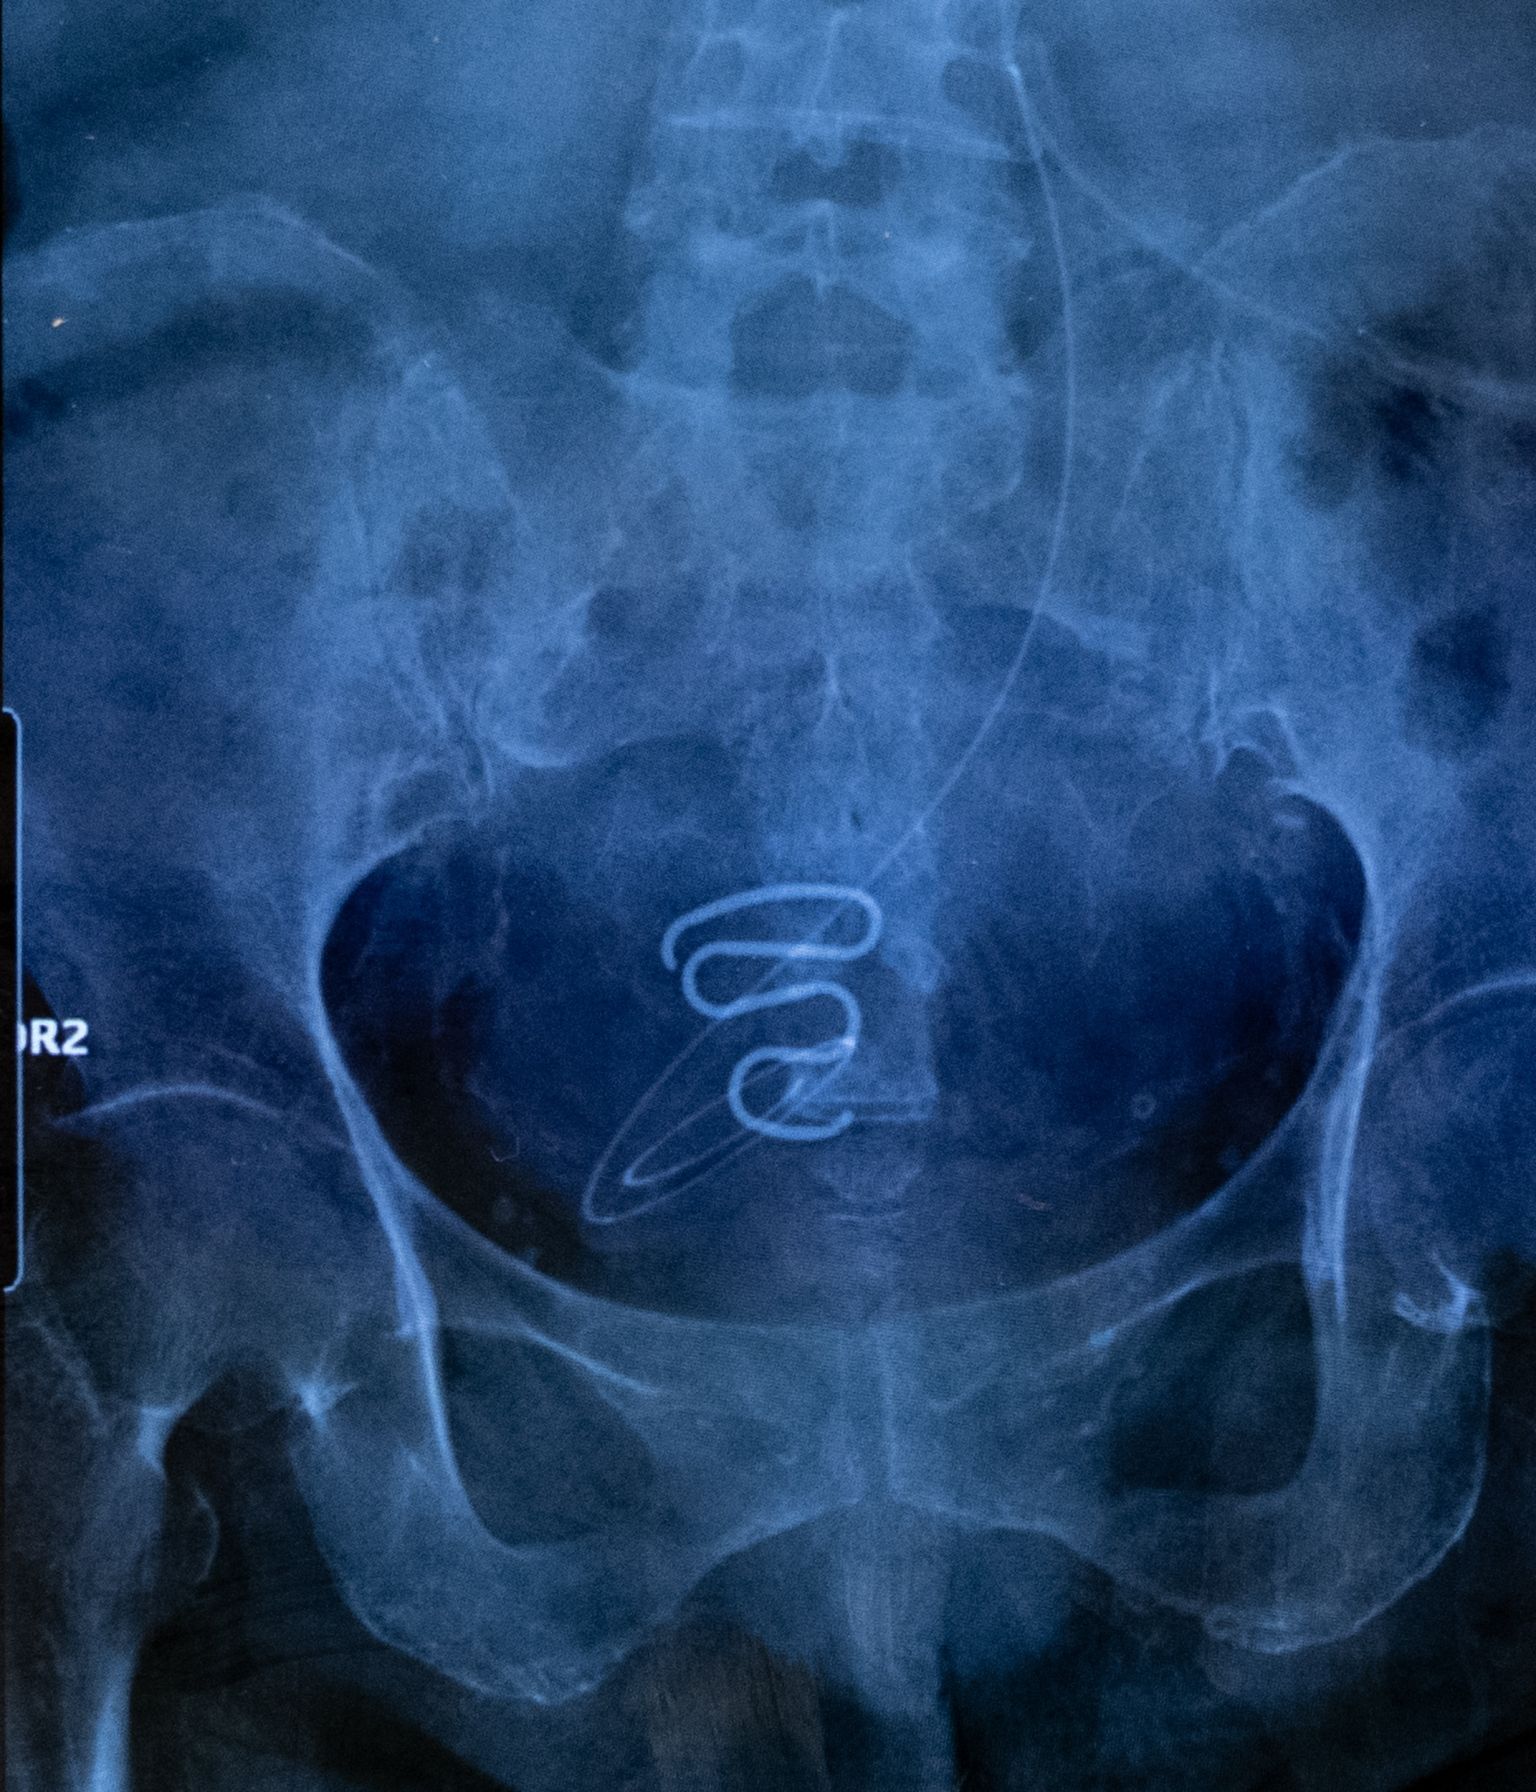

radiographie d’un stérilet spirale

Radiographie d’un stérilet utilisé durant la campagne de contraception forcée au Groenland. Des femmes ont été contraintes de retirer elles-mêmes ce dispositif, faute d’assistance médicale.

Ces stérilets en forme de spirale étaient beaucoup trop grands et inadaptés au corps de jeunes adolescentes, certaines âgées d’à peine 12 ans au moment de la pose. En plus des douleurs et des saignements, ils ont provoqué de graves infections, rendant certaines victimes définitivement stériles.